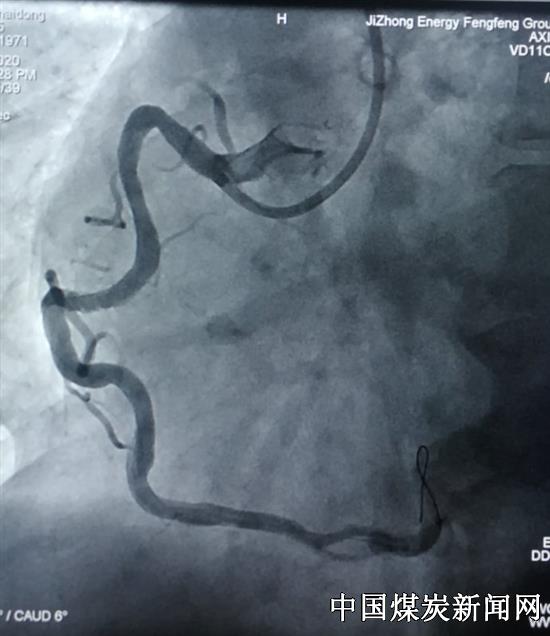

47岁的王先生因胸闷、胸痛、大汗夜晚就诊急诊科,心电检查:急性下壁、后壁、右室心肌梗死。心内一科主任王溥、副主任李玲及刘香格护士长接到急救通知后以最快的速度赶到,护送病人到介入导管室进行急诊冠脉微创介入术,冠状动脉造影示:右冠闭塞,患者阻塞血管极其粗大,但因血管极度迂曲,固定狭窄重,指引导管不给力,导丝无法通过,介入手术难度非常大。

王溥和李玲商议决定先给患者经指引导管给药进行冠脉内溶栓降低了出血风险。血管出现部分再通后,导丝终于通过了闭塞病变,到达了血管远段,成功地为病人在迂曲且狭窄最重部位植入了支架。这名患者右冠状动脉非常粗,梗死面积极大,如果不及时开通闭塞血管,患者死亡危险高,还会导致残疾。